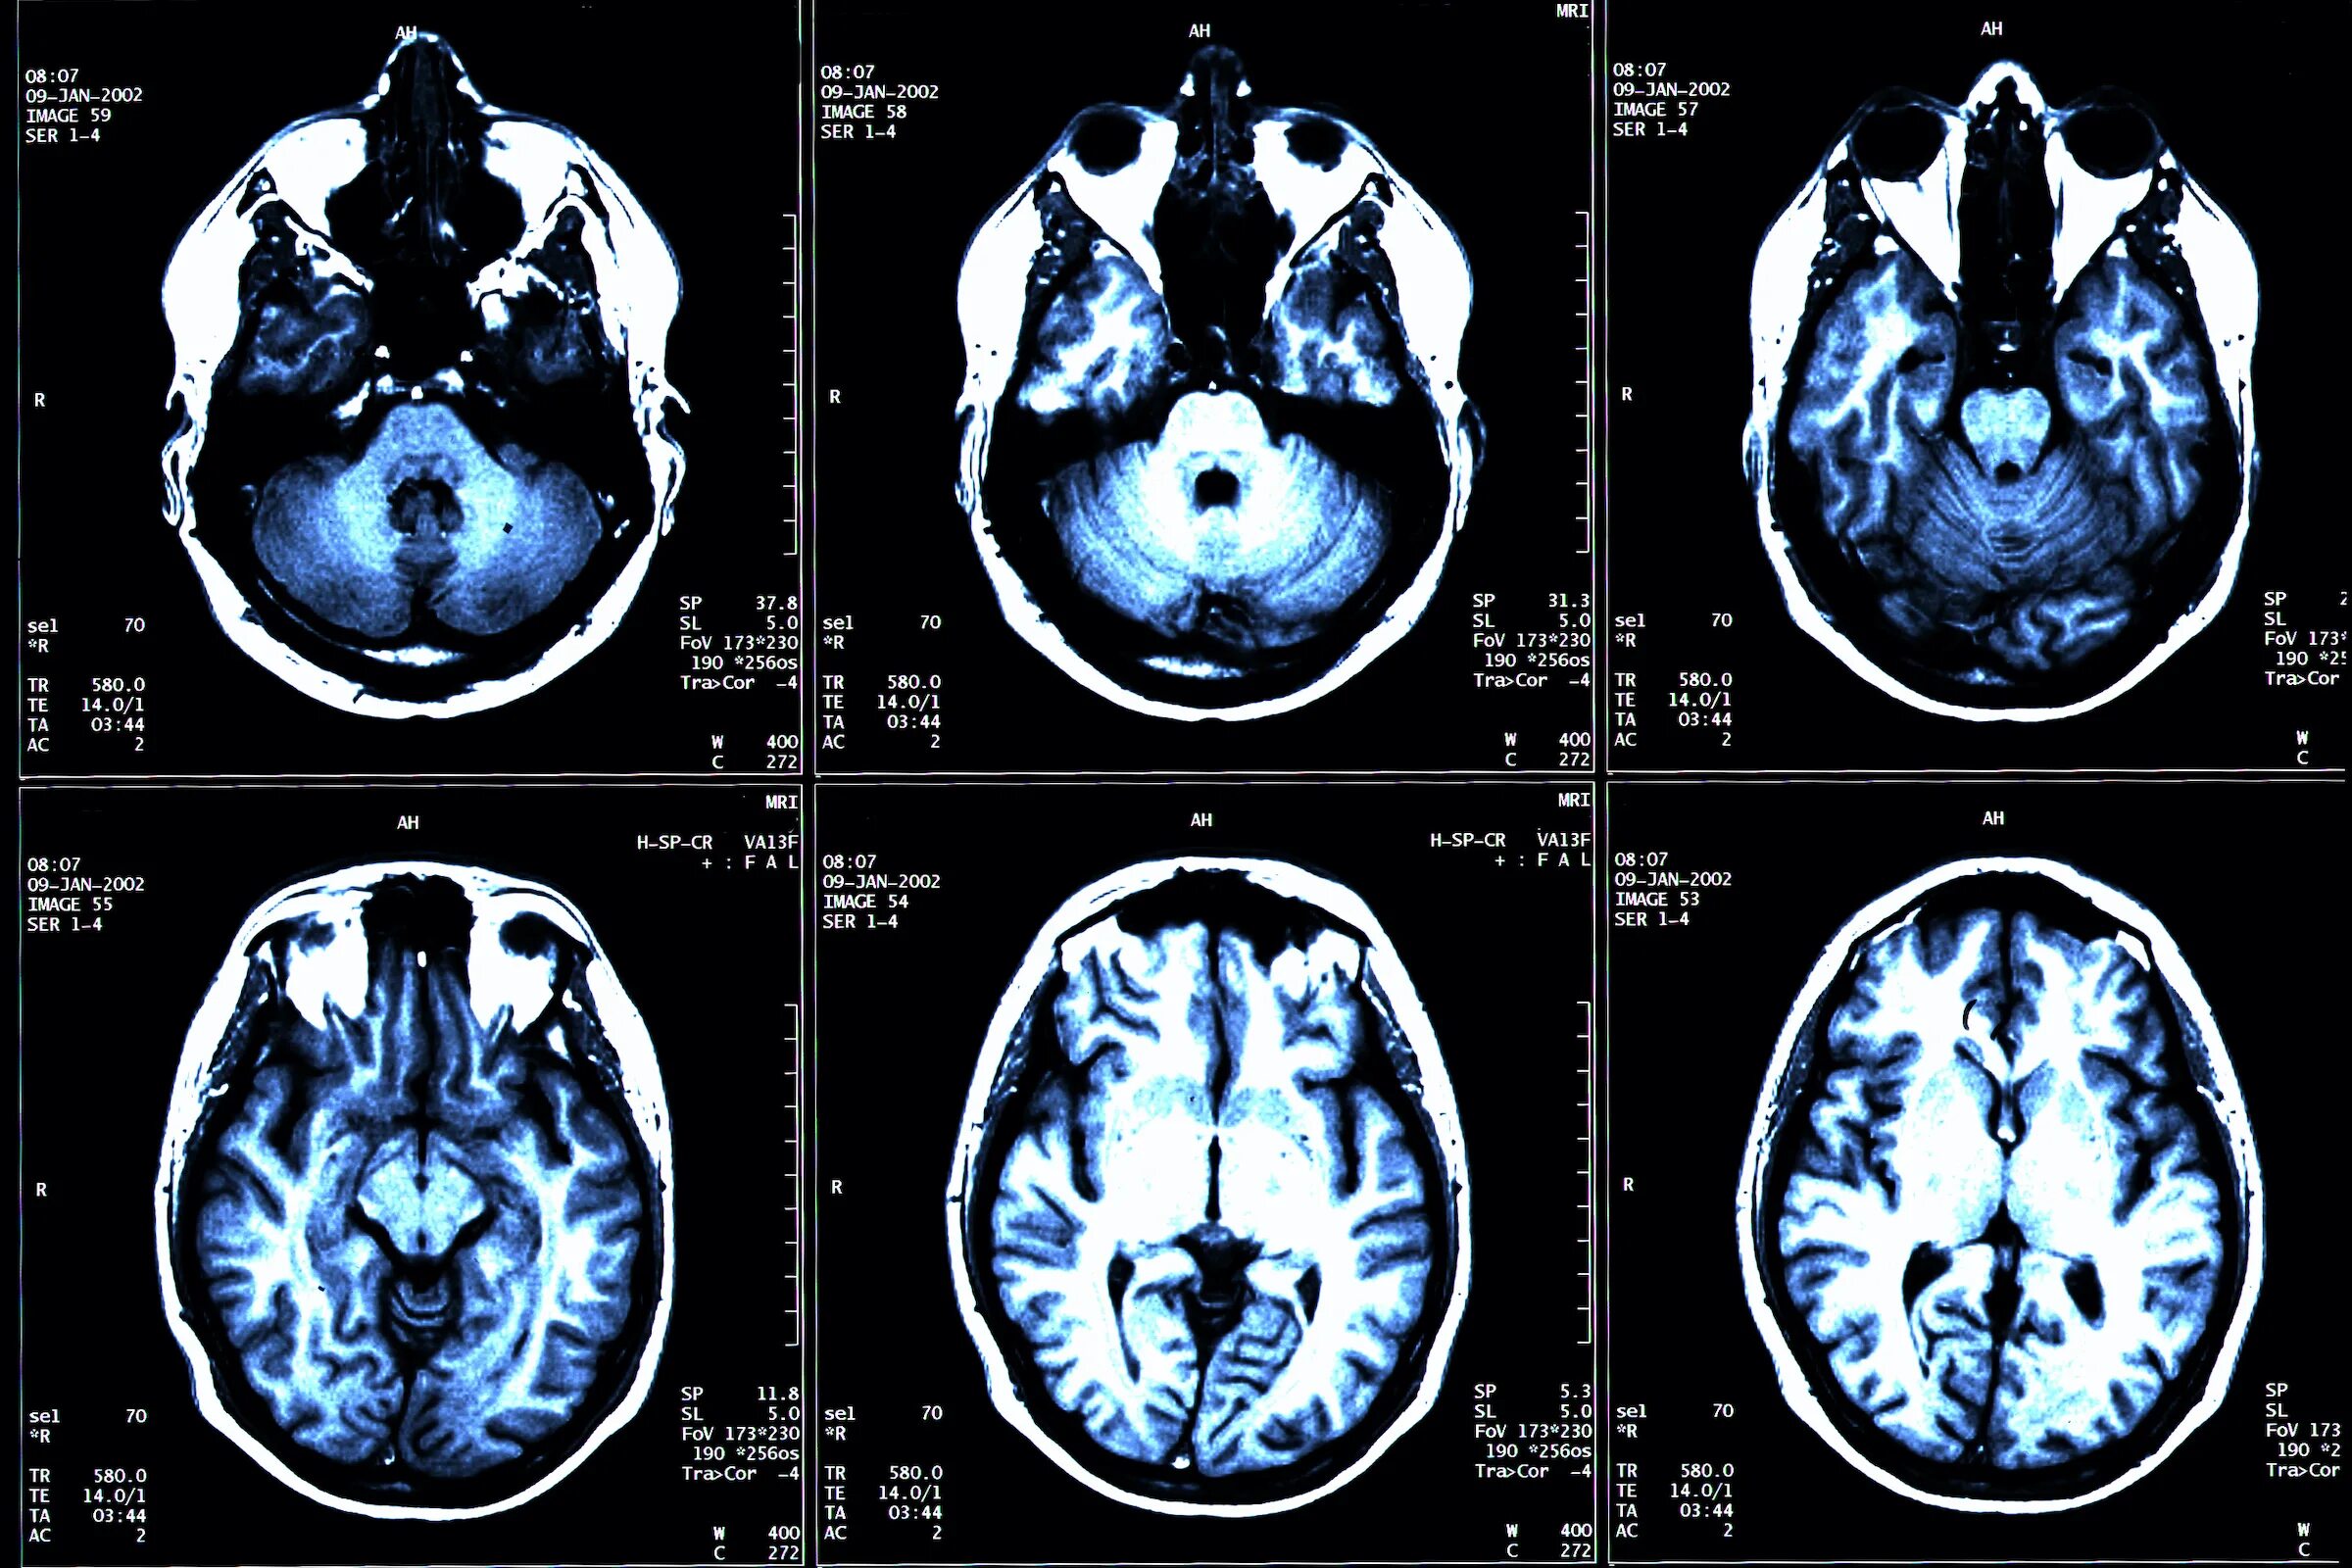

Ребенок асимметрия боковых желудочков